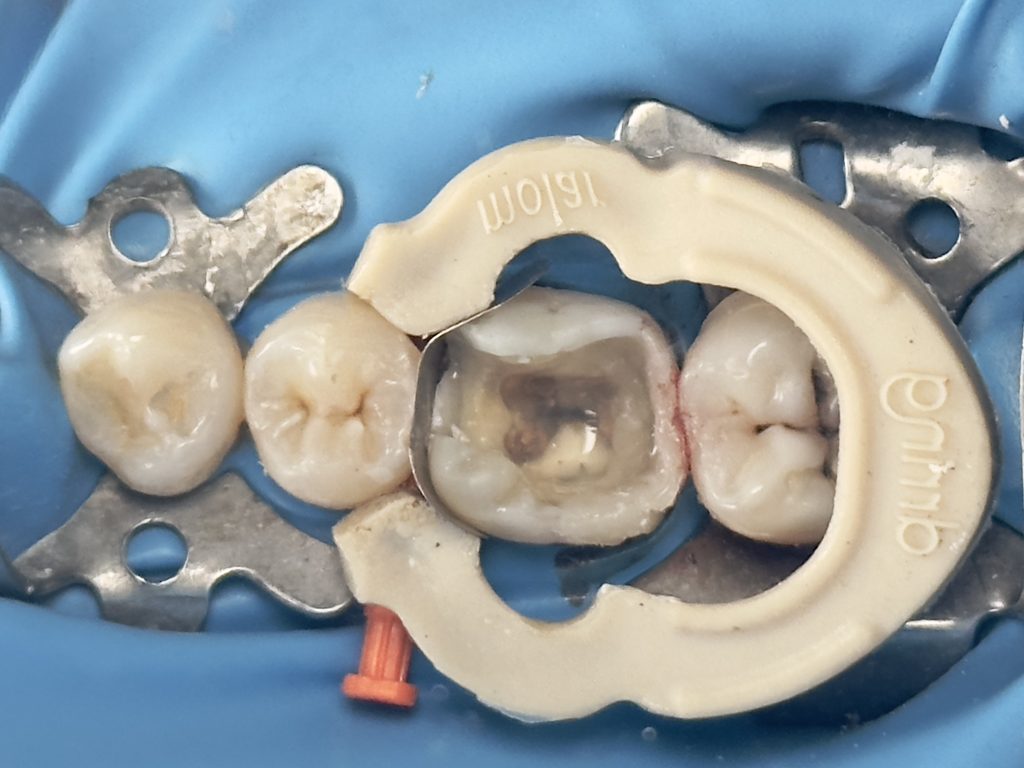

1st visit :-

-Complete amalgam removal

-gingival trimming of the inflamed gingival caused by over hanging margin

( tip : transfer the rubber dam strap between tooth no.6 &7 with blunt instrument to the contact between tooth no.5&6 rather than removing the entire RD sheet to trim the gingiva

then put it back to its position after the trimming) this controls the bleeding & saves time

-clean & neat margin

-IDS & RC

-DME (matrix sealed with teflon &diamond wedge)

-ever X posterior to increase fracture resistance